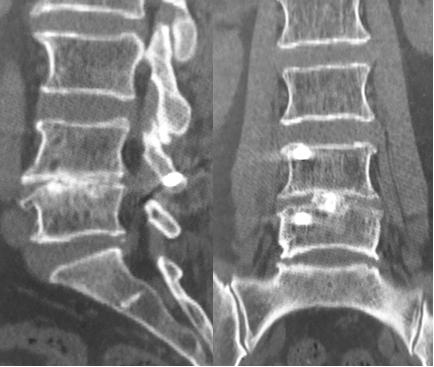

4,术后3个月,各项功能良好,行走自如。三维CT重建内固定在位,TFS螺钉完美穿越棘突、椎板、上下关节突和椎弓根。牛骨融合器完整,与植入的自体骨长为一体,发生融合,这种现象在金属及PEEK材料融合器很少观察到,可能说明生物材料的牛骨融合器有促进融合的作用。

更令人兴奋的是:仅仅110天左右(3月余),已经明确观察椎体间有明确的大面积融合骨桥形成(从椎体前至椎体后,从左至右均有大面积明确融合),这说明椎体间的融合可能在更早时间已经形成,可能是2个月甚至只是1个月左右就已经有明确的融合发生。

110天融合